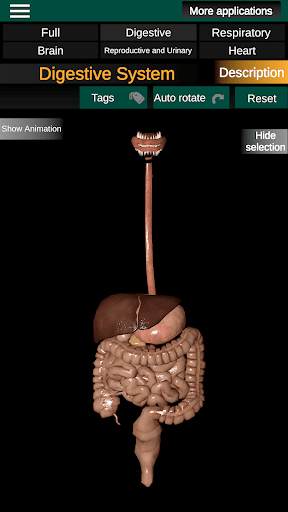

* Digestive system, including the stomach, small intestine, large intestine, and an animation of this system.

* Easy to access and navigate (zoom, 3D rotation).

* Hide or show information.

* Descriptions of each organ.